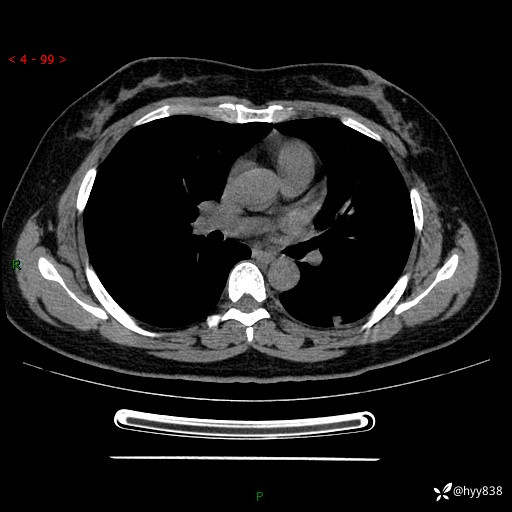

胸部CT复查+增强(2024.6)